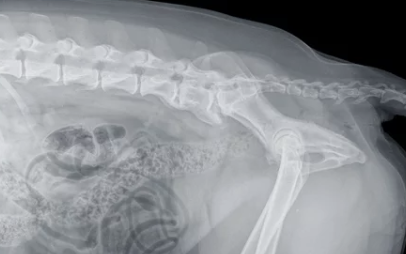

강아지 허리디스크(추간판 탈출증)는 척추 뼈 사이의 디스크(연골 조직)가 탈출하여 신경을 압박하는 질환이다.

✔ 정기적으로 신경 반응 검사 및 엑스레이 검사 받기